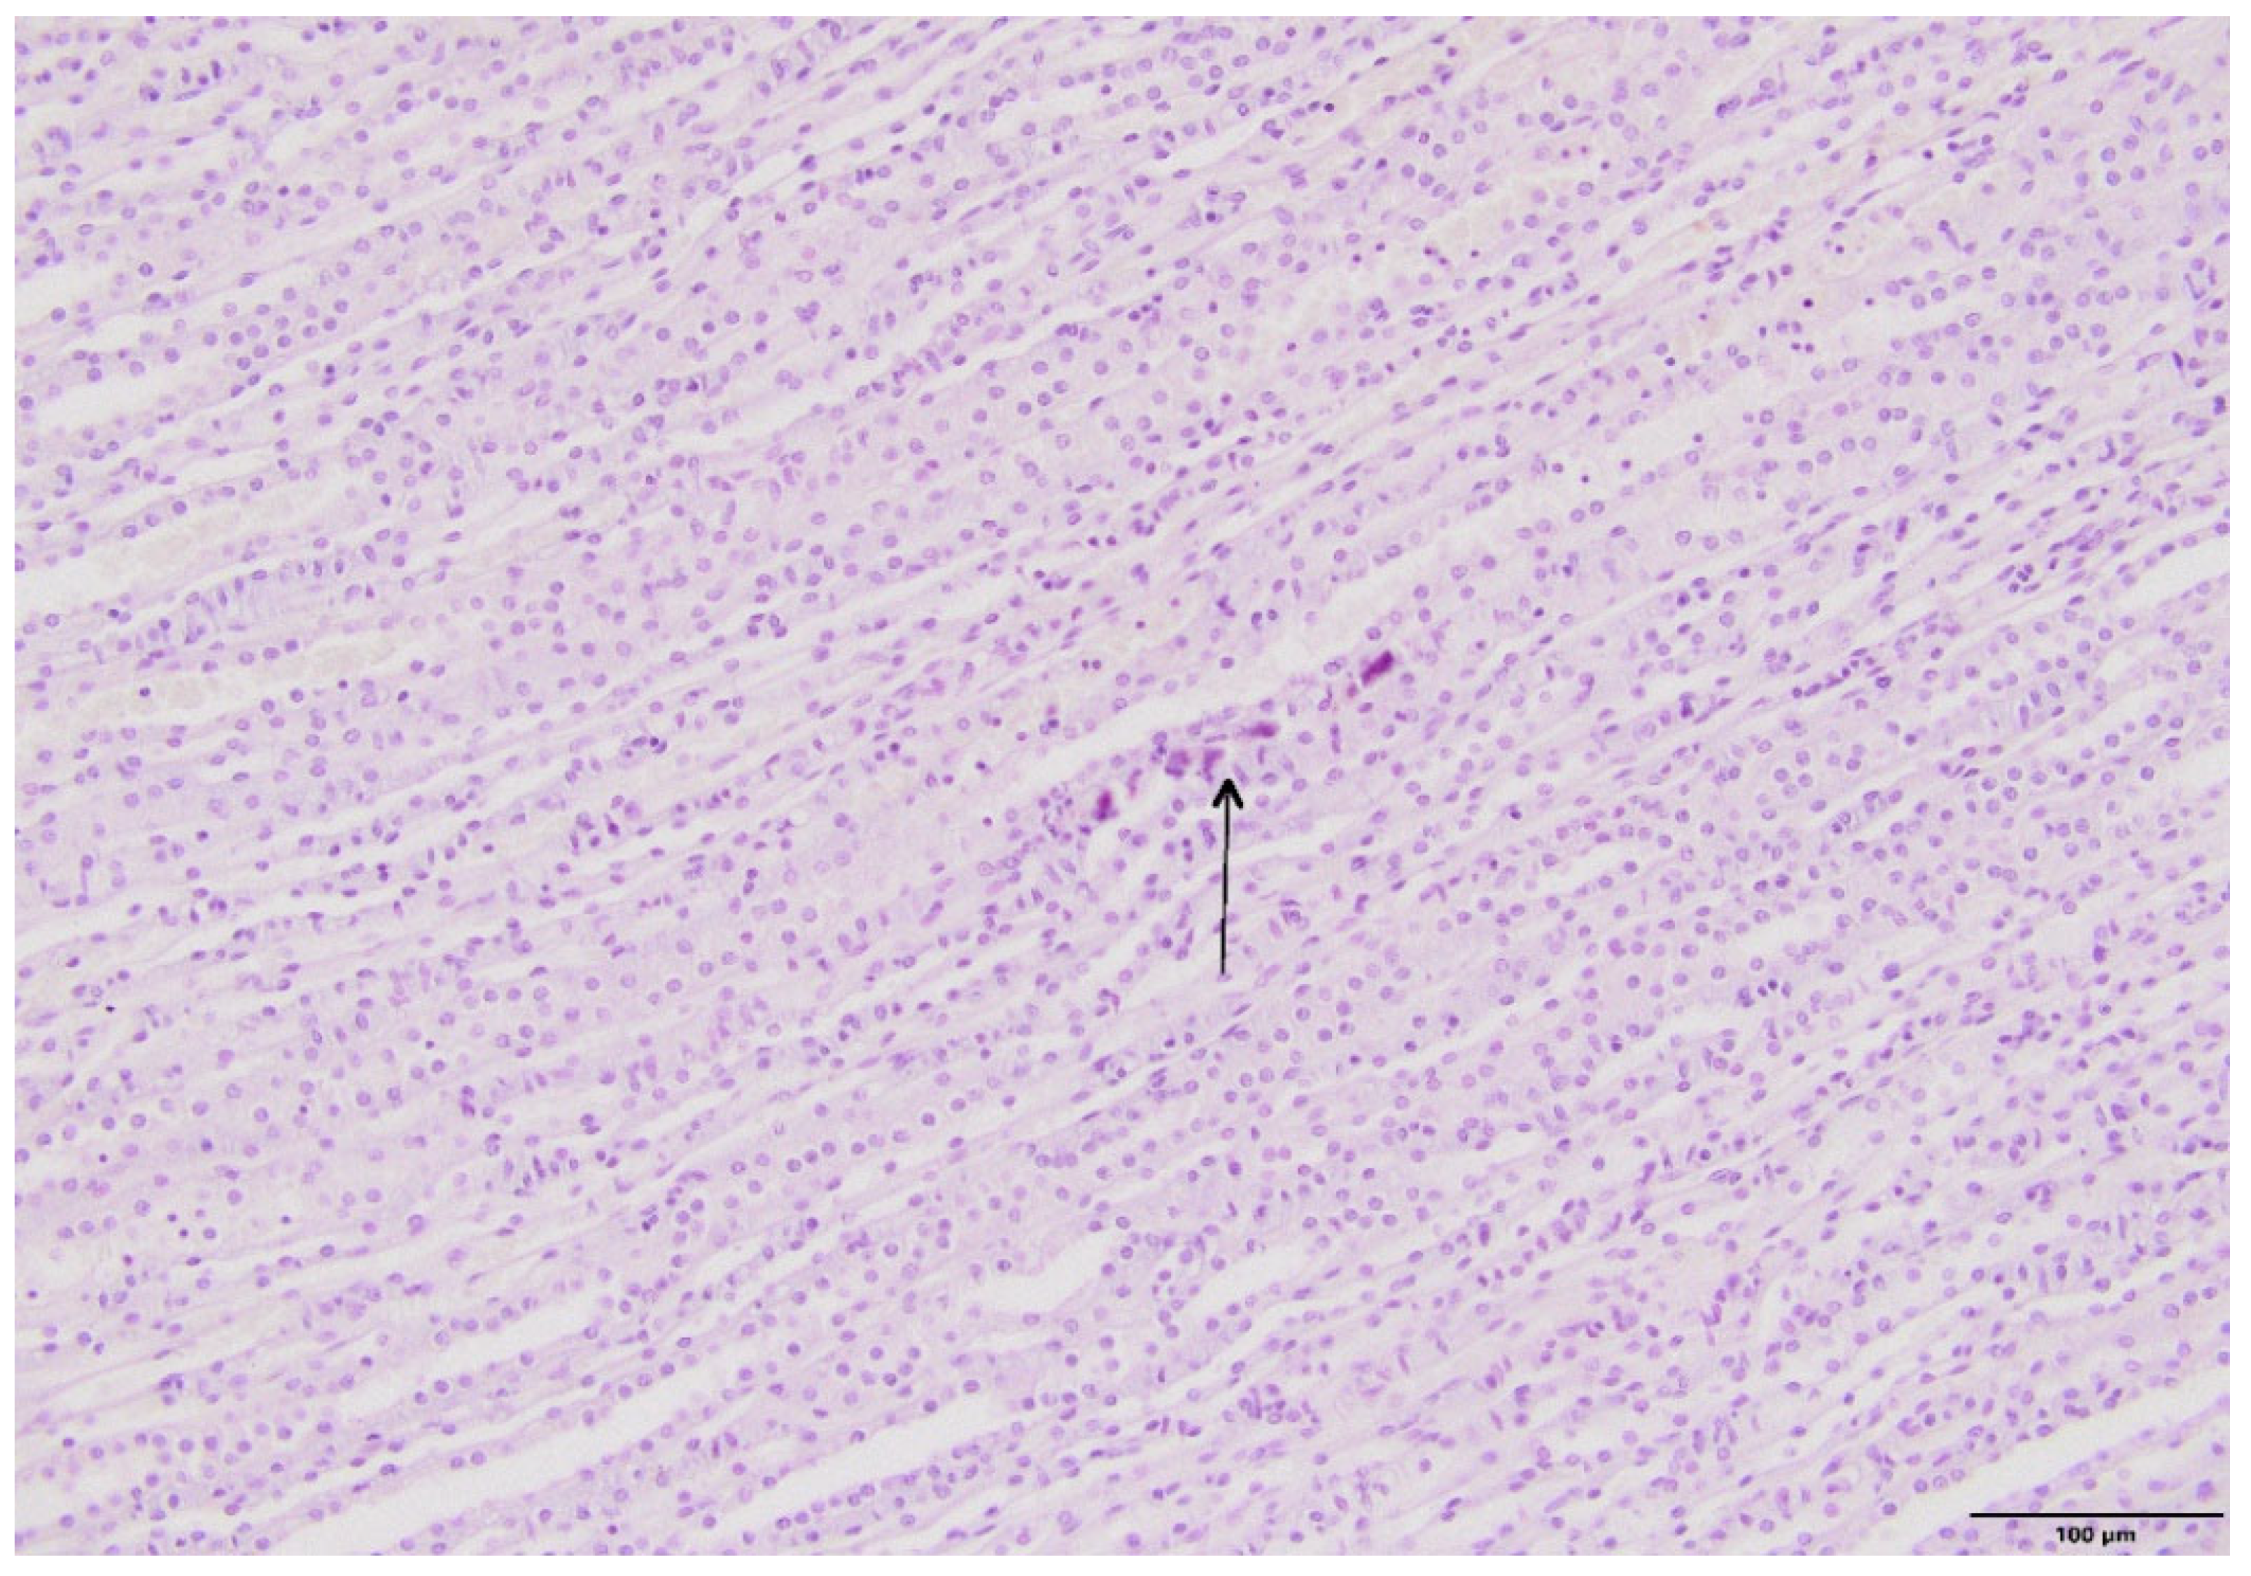

2.4. Kidney Histopathology